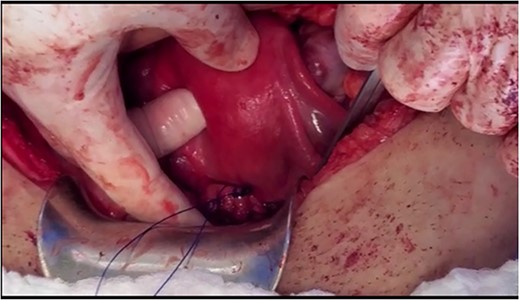

Under spinal anesthesia, supine position, the patient underwent laparotomy with a transverse skin incision and midline incision of the fascia. Exploration confirmed the pre-operative diagnosis. The retroperitoneal space was entered, and ureters were identified bilaterally. A window was opened (broad ligament) at the level of the uterine artery to ligate uterine arteries using ligasure, ureterolysis was done and both ureters were skeletonised down to the ureteric tunnel (as in radical hysterectomy). The uterosacral ligament and cardinal ligament were ligated using ligasure, at the level of the cervico-vagina junction. An anterior colpotomy was done after the dissection of the bladder and creation of the bladder flap, and the anterior colpotomy was extended laterally from each side by using ligasure with careful attention to keep the ureters away. The circumcision of the cervix was completed by using Heaney clamps at the vaginal angles. The uterus was mobilised along with the cervix and the myoma and completely separated from the vagina (Fig. 1). At this point, cautery was used to amputate the cervix with careful attention to maintain the integrity of the infundibulo-pelvic ligament (Fig. 1). The uterus was sutured to the vagina with the box technique, where the posterior aspect of the vagina and cervix was sutured, followed by the lateral and anterior wall. After that, one proline permanent suture was used as a cerclage, used to support the uterus for future pregnancy (Figs 2 and 3).

The cervical myoma attached to the uterus with intact infundibulopelvic ligament.